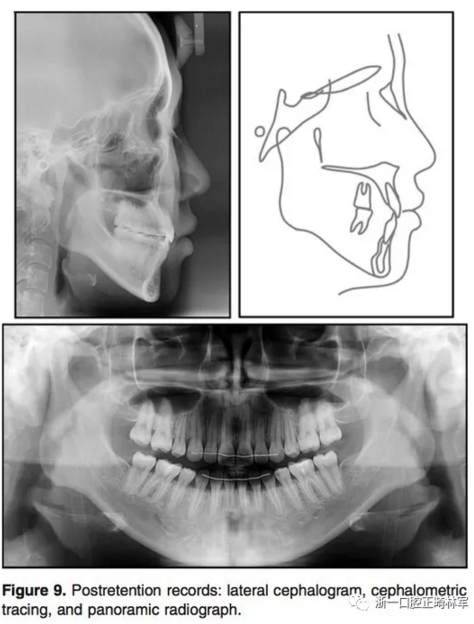

9.jpg

10.jpg

1年的保持,示咬合和面型保持良好。治療后和保持后的重疊像示上下切牙輕微唇傾,導(dǎo)致覆蓋有所增加。上下第一磨牙的位置變化微乎其微。